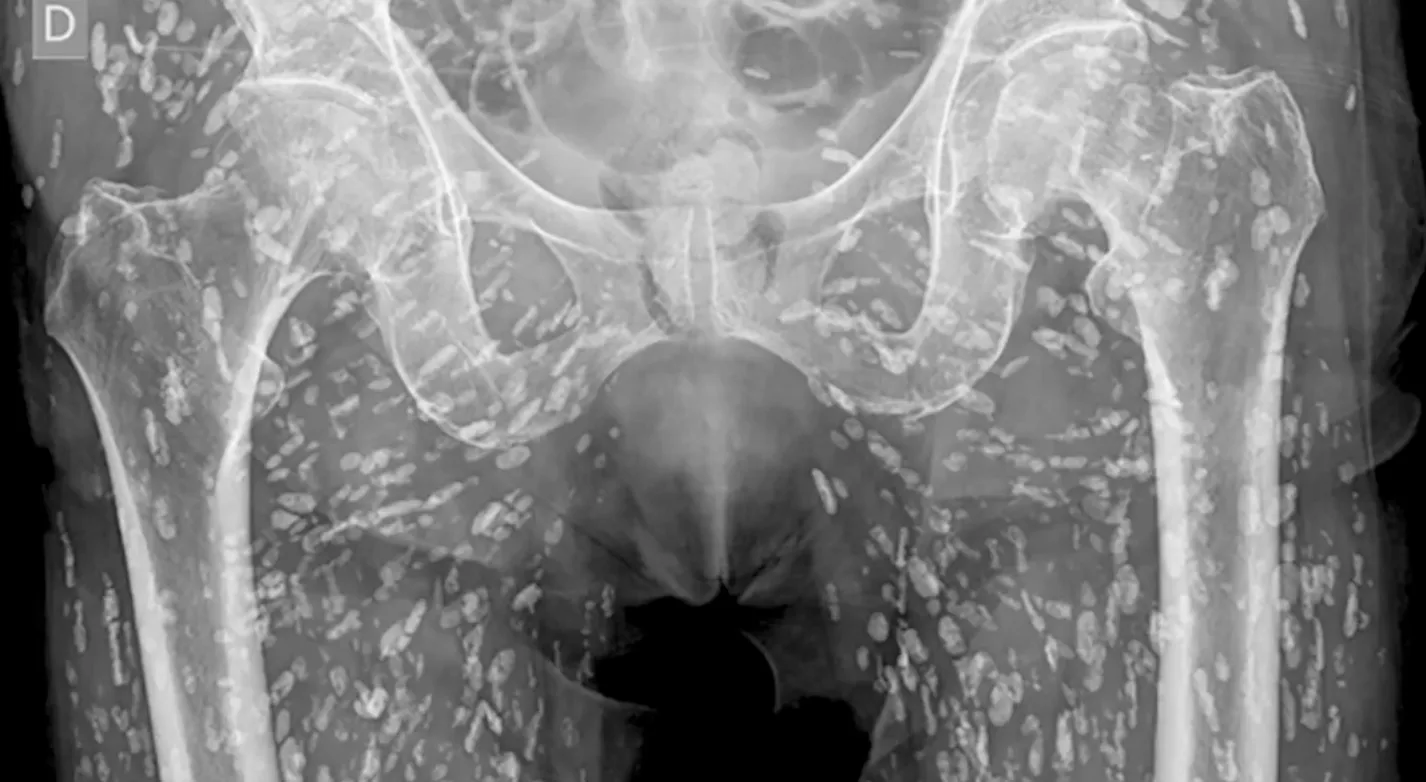

‘This is one of the most insane X-rays I’ve ever seen.’

Sam Ghali, an Assistant Professor in Emergency Medicine at the University of Florida, shared the shocking images in a post on X, saying it was “one of the most insane X-rays I’ve ever seen.”

Speaking over the X-ray pictures, Dr Ghali explained that the small white marks were dozens of calcified tapeworm eggs, which had been laid in the soft tissue of the man’s pelvis.

The parasitic worms had made their way into the man’s body after he ate undercooked pork, a condition known as cysticercosis.

This is where larval cyst of taenia solium make their way into the body. Once there, they can burrow into muscular and soft tissue and travel “throughout the entire body,” Dr Ghali said.

He explained: “These cysts can travel anywhere throughout the entire body, heavily to the muscular and soft tissue of the hips and the legs.

“This condition comes from when the patient eats undercooked, or raw, pig. If just in the pelvis, they don’t pose a life-threatening problem. The problem is if they travel to the brain and lodge there.